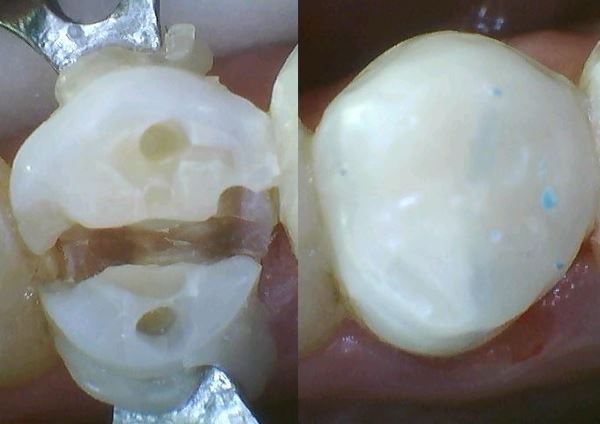

links 13:36 Uhr: Die Belastung liegt nur auf den Höckern.

Mitte 15:53 Uhr: Unter dem Amalgam sieht man: alle drei Höcker haben von aussen unsichtbare Dentinrisse. Sie wurden gekürzt.

rechts 14:21 Uhr: Das fertige Komposit mit den Farbpunkten in der Mitte.